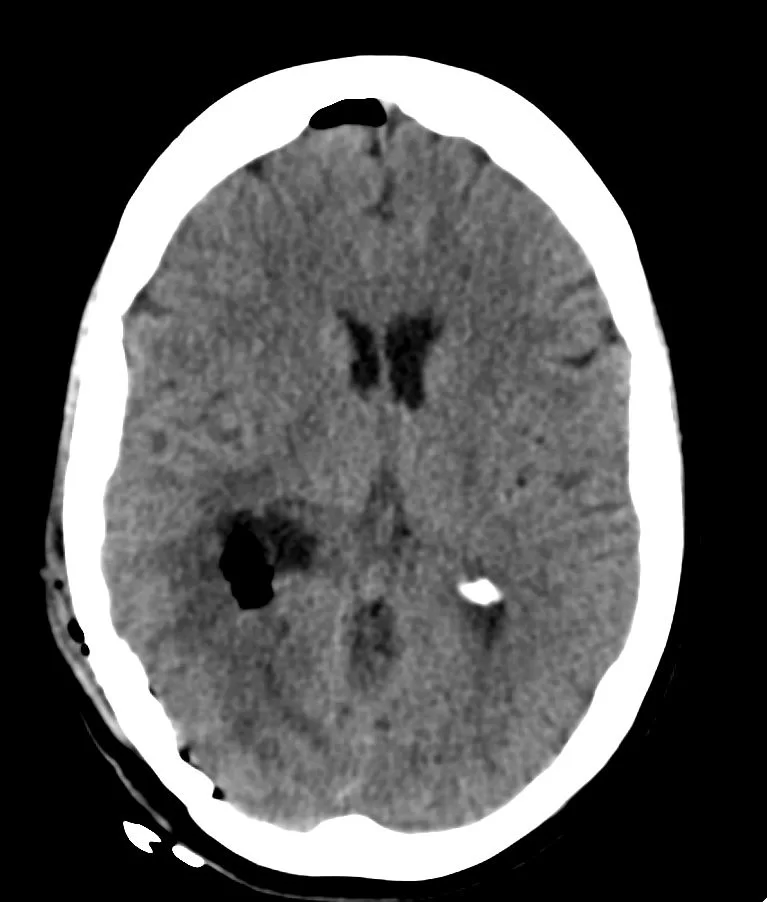

Η μετεγχειρητική αξονική τομογραφία εγκεφάλου δείχνει πλήρη αφαίρεση της βλάβης. Η ιστολογική εξέταση επιβεβαίωσε τη διάγνωση (μηνιγγίωμα WHO I).